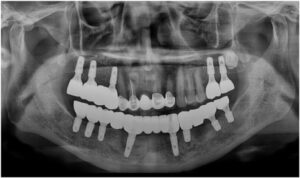

정밀한 검사를 위해

파노라마 사진을 촬영해 보았더니

아래턱 치아들이

심각한 골흡수를 보이고 있는

만성 치주염 상태로

전체 발치가 불가피한 상황이었습니다.

파노라마 촬영을 통해

임플란트가 정확한 위치와 방향으로

식립 된 것을 확인하였습니다.

모든 치료가 마무리된

파노라마 사진과

구강 내 사진인데요.